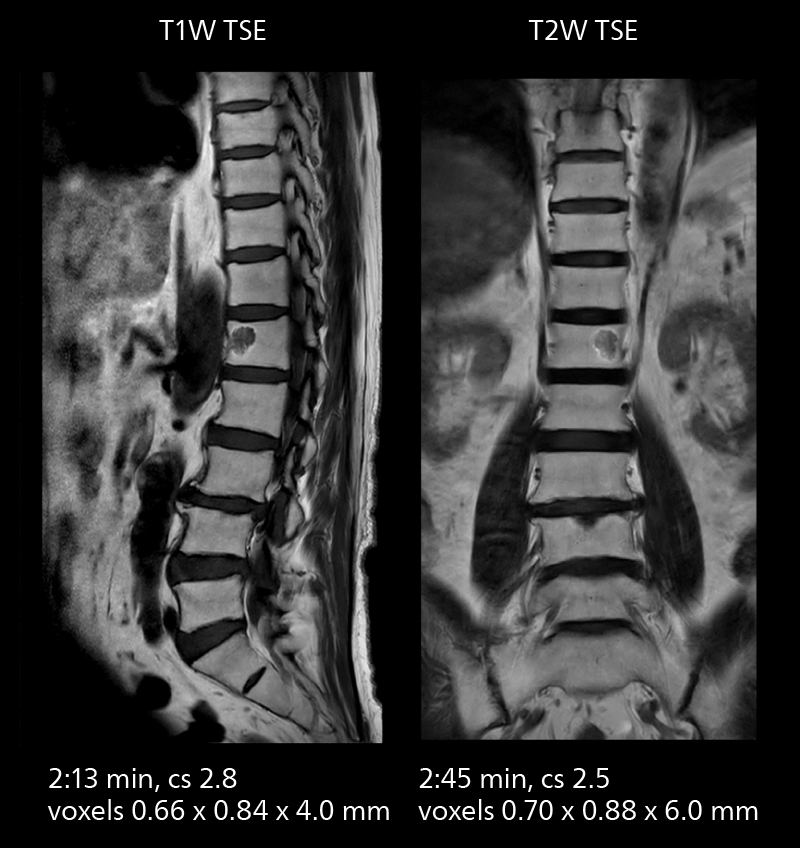

With SmartPath to Elition X the team can obtain excellent quality DWIBS imaging and reduce imaging time. Other sequences also fit in the examination slot. This case shows left paravertebral neurogenic tumor and Th10 vertebral hemangiomas.